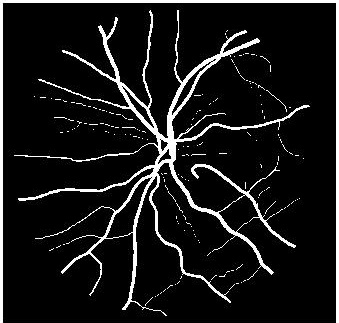

4.2 Retinal Blood Vessel Segmentation Results

We present retinal vessel segmentation results on the DRIVE [16], STARE [6] and CHASEDB1 [5] datasets with , and images respectively. Original images and manual annotations () are downsampled by to get and sets of from methods trained on [2]. and the sets of were used to train different state-of-the art U-Nets for vasculature segmentation [1]. The average accuracy () and sensitivity () for is summarized in Table 2. Better ISR methods should give higher vessel segmentation accuracy and performance of gives a lower bound on the segmentation error. ’s performance is closest to , and establishes its superiority over all competing methods. Figures 4 (a)-(h) show results of vessel segmentation on an example image. ’s performance is most similar to as is evident from the areas of inaccurate segmentation highlighted by yellow arrows. Most of the methods do not segment the finer vasculature structures, while SSR and SR-RF are unable to segment some of the major arteries.

| (a) | (b) | (c) | (d) | (e) | (f) | (g) | (h) |